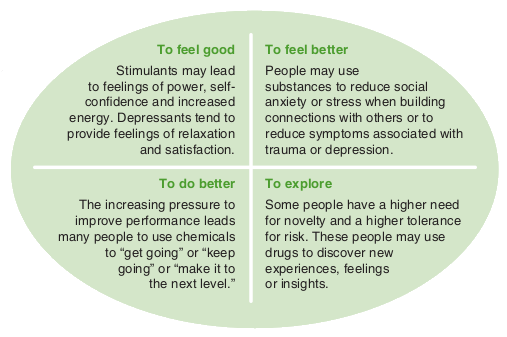

Understanding Substance Use A Health Promotion Perspective Here To Help

Understanding Substance Use A Health Promotion Perspective Here To Help